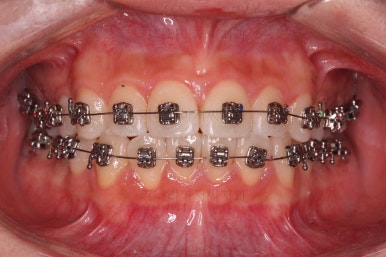

이번에 사용한 장치는 엠파워메탈이라고 하는 자가결찰(철사를 잡아주는 뚜껑이 달려있는) 메탈(금속 성분) 장치였어요.

매우 장점이 많으나 심미성과 재료제작 비용 때문에 상대적으로 저렴한(이것도 장점일 수 있죠.) 장치입니다.

장치를 부착했을 때 입이 나오는 느낌, 웃을 때 느낌은 참고해 주세요.